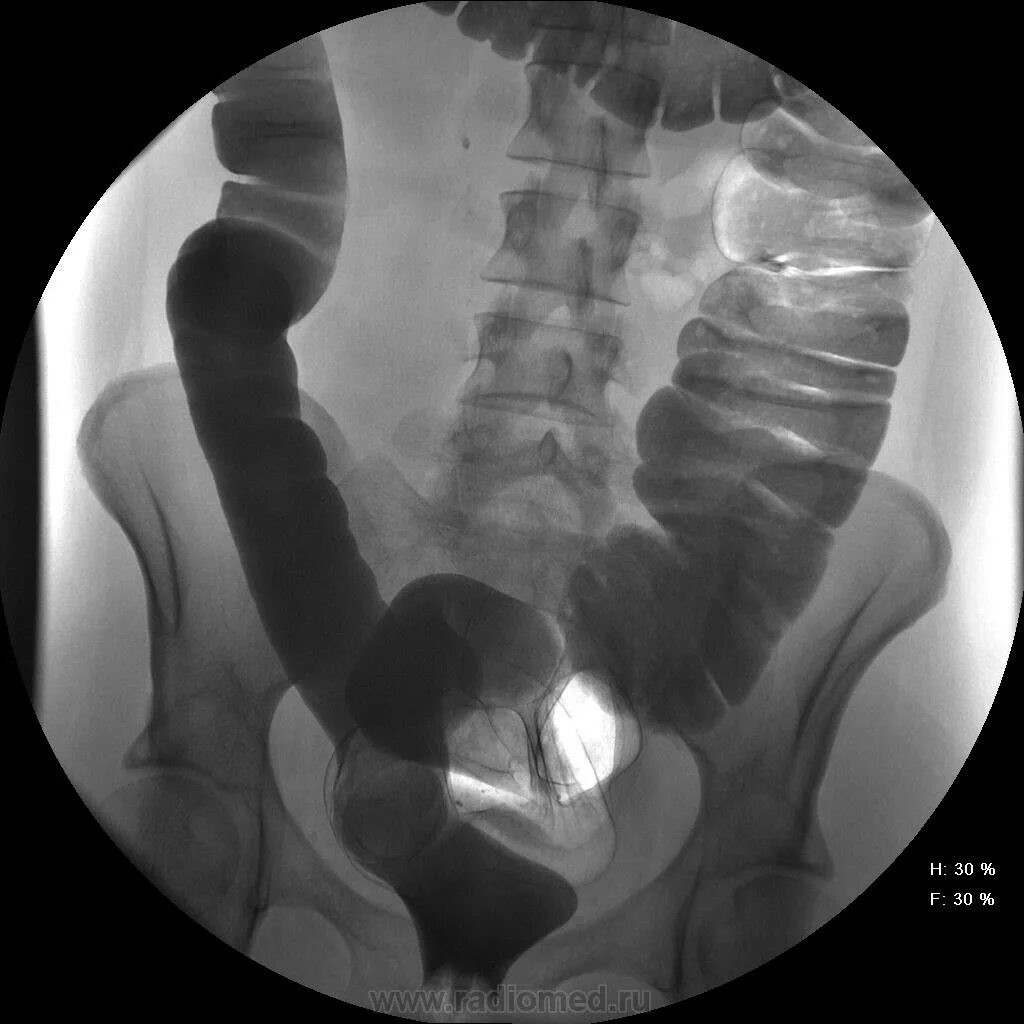

Рентгенодиагностика заболеваний толстой кишки. гаустрация сигмовидной кишки. ирригоскопия патология.

Гаустрация толстой кишки механизм. брыжейка сигмовидной кишки. восходящий отдел слепой кишки. трансверзоптоз ободочной кишки.

Гаустрация петель толстого кишечника. сглаженность гаустрации сигмовидной кишки. гаустрация толстой кишки что это.